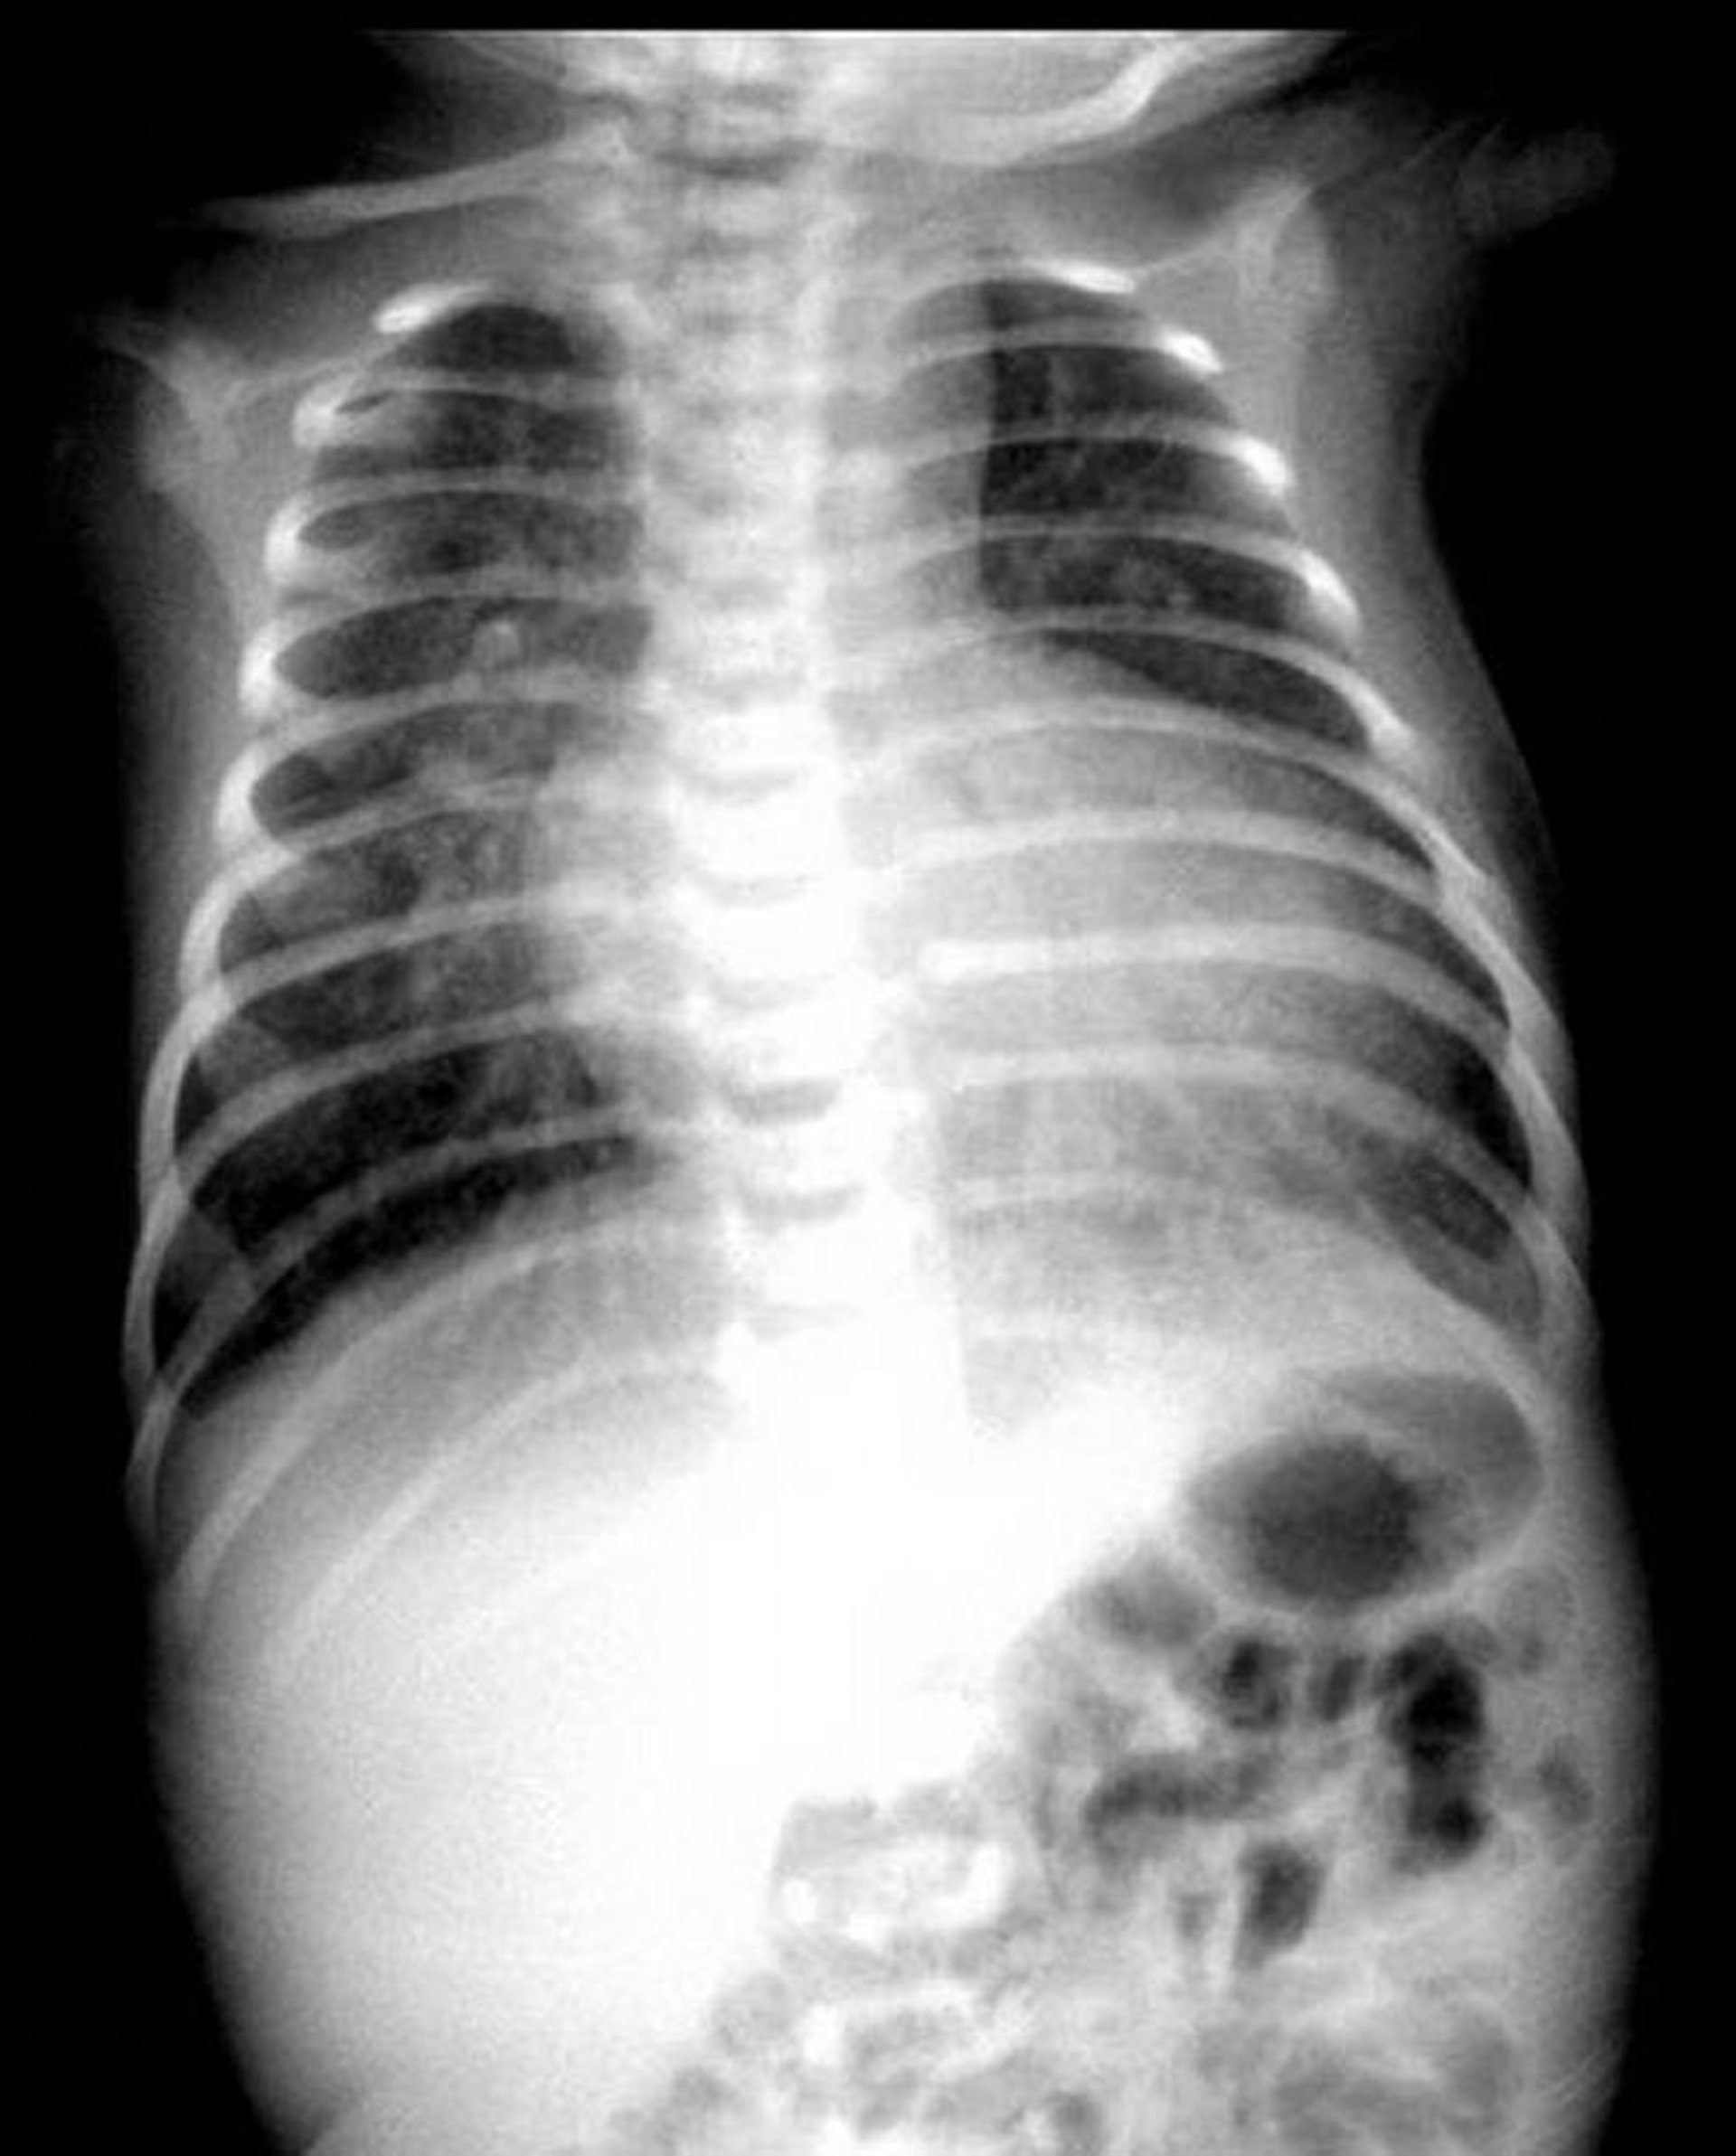

Radiografía de tórax que muestra el aspecto clásico de huevo en una cuerda en un paciente con transposición de las grandes arterias.

Imagen proporcionada por Jeanne Marie Baffa, MD.